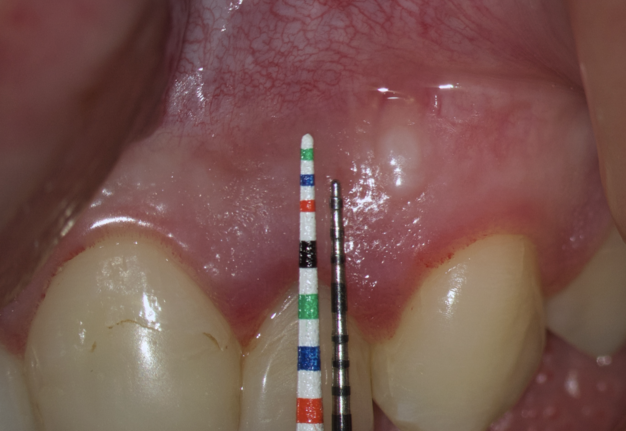

We transfer this distance is transferred to a metal probe and fixed with an endodontic stopper. Next, we take a plastic probe and substitute it near the zenith of a tooth on which the intervention will be performed at a mark of 6 mm (3 mm must be retreated to perform a submarginal incision and another 3 mm is needed for the formed flap to overlap healthy bone tissue) (Fig 8).

We compare the lengths of the plastic and metal probes. The first option is when the metal probe is above the plastic one, then we can assure that the incision and the Ochsenbein-Luebke flap will accurately cover the bone defect and the submarginal incision is safe (Fig 9).